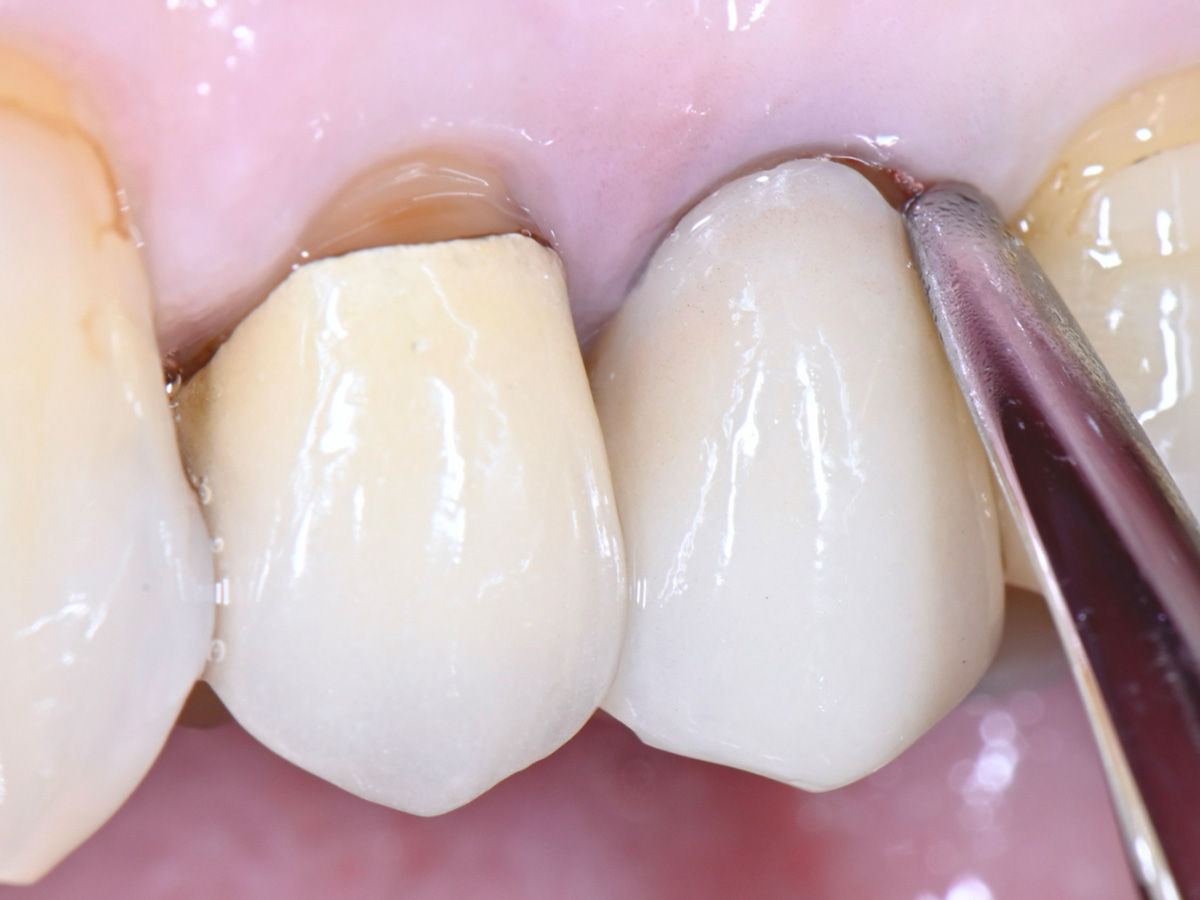

Abbildung 2

Klinische Ausgangssituation